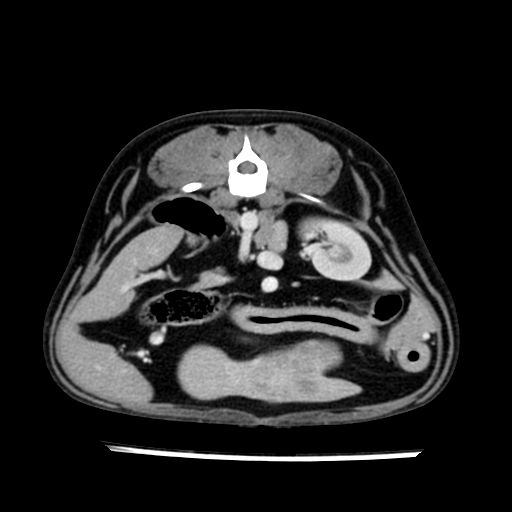

prescritto esame TAC

sequenza immagini limitata al fegato reni e surreni

le immagini ecografiche rispetto alla tac datano circa 7 mesi prima ,le surrenali sono normali nonostante il test acth sia risultato positivo .all’esame TAC dopo diversi mesi risultano aumentate armonicamente nel volume e si individua un forte sospetto di adenoma ipofisario .

sospetto adenoma ipofisario vs. meno probabilmente meningioma della base; intertiziopatia polmonare; lesione espansiva epatica, verosimilmente del lobo laterale sinistro, di sospetta natura neoplastica; lesioni spleniche di natura da definire; iperplasia/ipertrofia delle ghiandole surrenali, bilateralmente; vertebra di transizione del rachide toracico; tenosinovite cronica del muscolo bicipite brachiale di destra.

la tac dopo 7 mesi permette misure tridimensionali 5,2 x 9,2 x 4,5 cm (forma piu’ allungata )